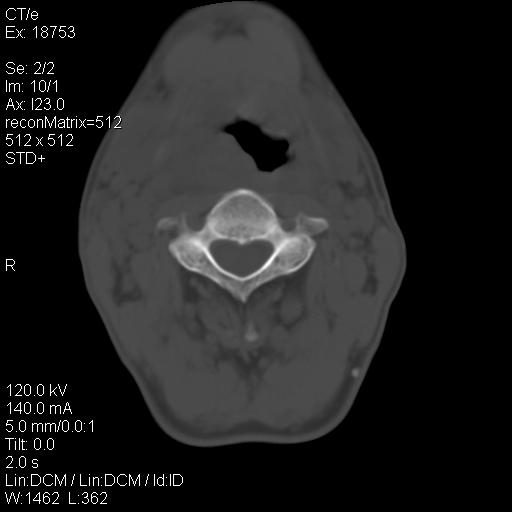

标题: CT21693:男 58岁 右侧咽部疼她2天余 PE:右侧扁桃体肿大 压痛 [打印本页]

标题: CT21693:男 58岁 右侧咽部疼她2天余 PE:右侧扁桃体肿大 压痛

弥漫性肿胀,与周围组织分界不清,发病急,有明显症状,考虑:感染性病变!

弥漫性肿胀,与周围组织分界不清,发病急,有明显症状,考虑:感染性病变! 抗炎后复查。

右化脓性扁桃体炎症伴咽后壁脓肿形成.